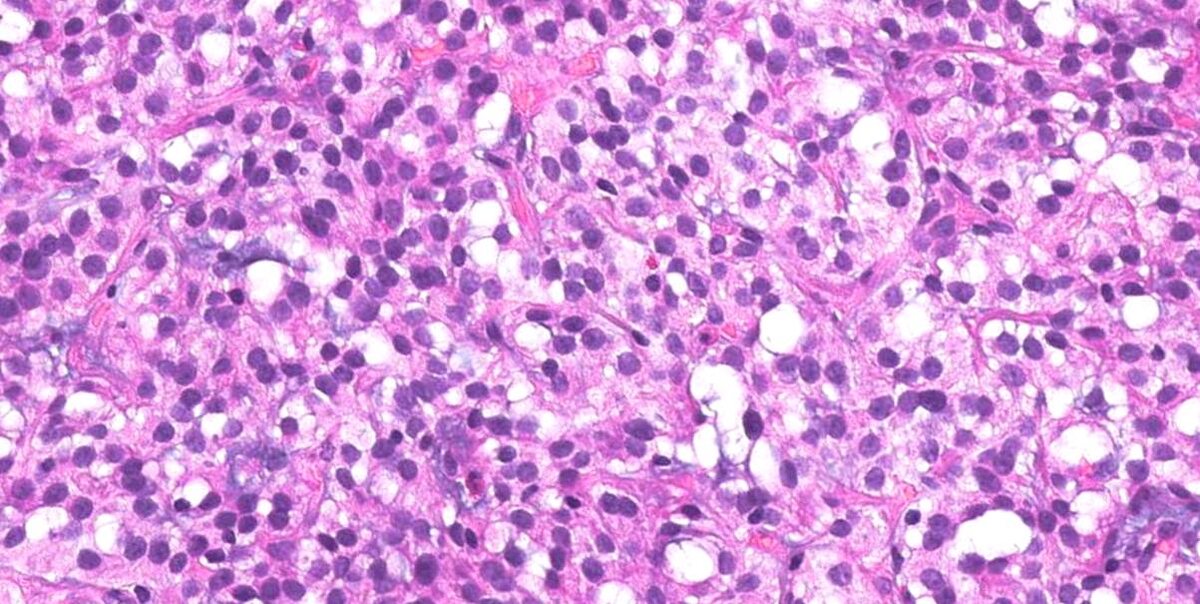

Гистофото НЭО 1 типа из предыдущего поста, любезно предоставлены Мариной Юрьевной.

Удалил обычными биопсийными щипцами, радикально. Необходимо индивидуально подбирать метод удаления в каждой конкретной ситуации. Главные критерии — радикальность и безопасность.

Здесь наглядно продемонстрировано, почему это образование НЕ подслизистое (субэпителиальное).